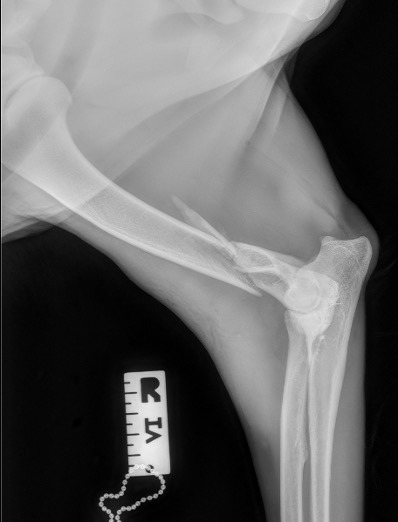

Exemple 1 :

Figure 1 : Pré-op